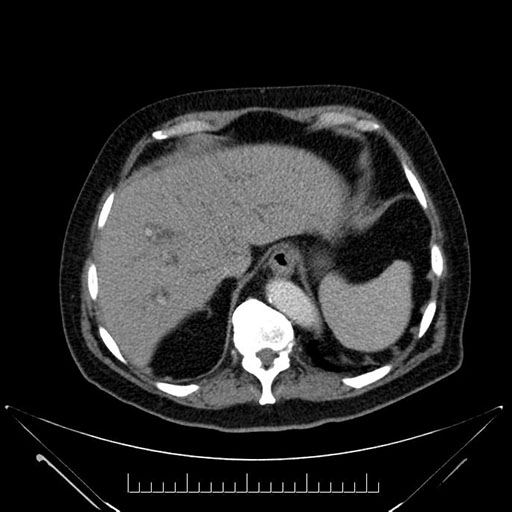

Whipple (pancreaticoduodenectomy) [case 7]

Axial - 3 months prior

Imaging analysis

Based on your CT findings, which issue(s) would give reason for "planned slowing down moment(s)" in this case?

Considering a standard Whipple procedure, what step(s) of the operation would you do differently in this case?